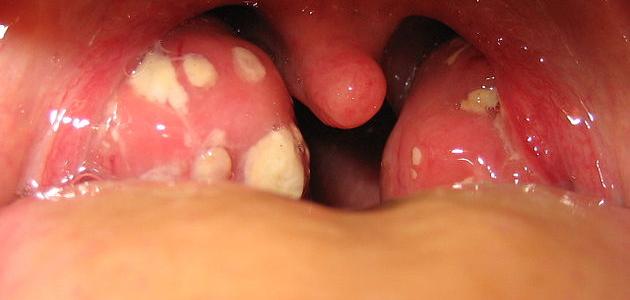

- يودي الى احمرار اللوزتين وحدوث وضعية من الانتفاخ فيهما.

حتى يكون الطبيب قادرا على تشخيص وضعية التهاب اللوزتين، فانه يقوم باخذ عينة من حلق العليل لاغراض الزراعة، ثم يرسل تلك العينة الى المختبر، وهذا للتاكد اذا كان المسبب مسببا بكتيريا او فيروسيا لتلك الوضعية المرضية المنتشرة. اما فيما يتعلق لعلاج مرض التهاب اللوزتين فانه يعتمد اعتمادا رييسيا على نوع المسبب لذلك المرض، فلو كان المسبب من النوع الفيروسي فان الاعراض تذهب على نحو تلقايي، اما ان كان المسبب من النوع البكتيري ففي تلك الوضعية قد يقوم الطبيب المعالج المختص بمثل تلك الحالات بوصف نوع من الادوية؛ كالمضادات الحيوية التي تعاون على التخفيف من حدة الاعراض المصاحبة لمثل تلك الوضعية المرضية وعلى راسها الالام المختلفة، والحرارة المرتفعة، وفي عدد من الحالات قد يقوم الطبيب بعملية استيصال للوزتين.